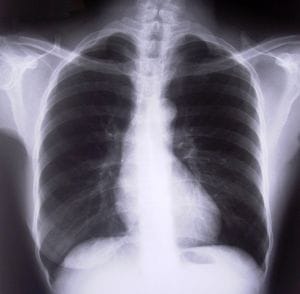

First, we need to understand that this is not a fringe issue. About one in five adults in America has had some kind of medical device implanted into their bodies for one reason or another. That’s roughly 20 percent, so this is not a minor problem.

Finally, the Consumer Report watchdogs looked at cardiac devices – mainly, defibrillators. In the last three years, nearly 30,000 people have died or been hurt as a result of usage of these devices. In most cases, it has to do with the wires that connect to the heart muscle.